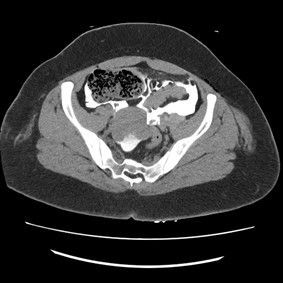

CT Imaging

Management

- Non-operative management in grade I to III renal injuries, regardless of mechanism

- Surgical Exploration in Grade IV and V renal injuries